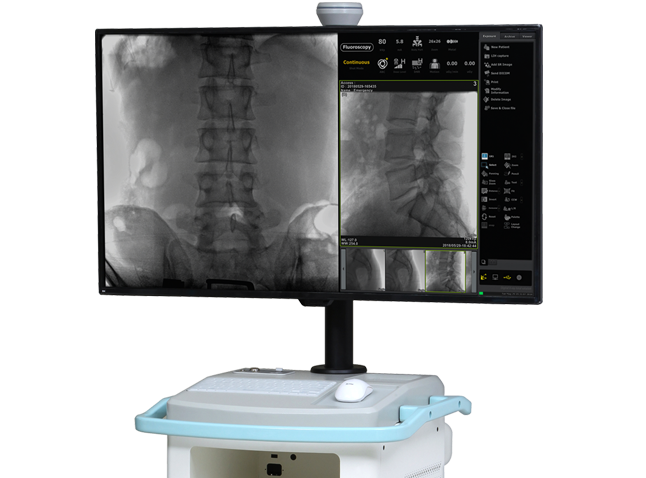

User-friendly 10.4" touch screen operation panel enables two-way communication between doctor and operator by using live image.

ZENIS™ software provides a total solution from operation, image storage, and management.